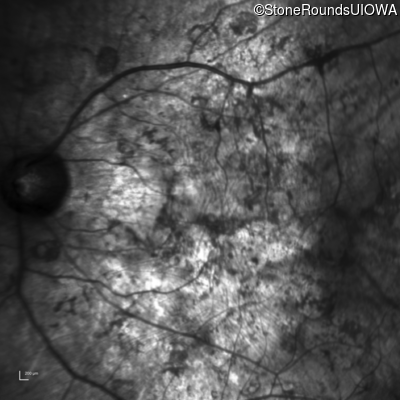

Infrared Fundus Photograph - Left - Hand Motion sc

Exemplar